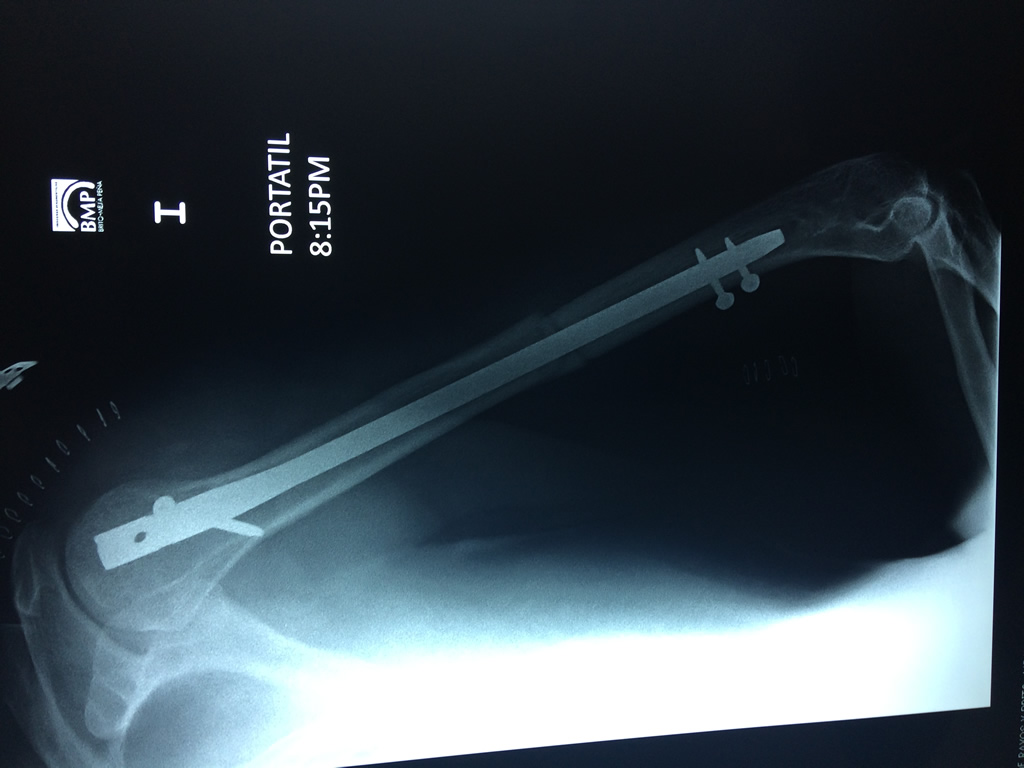

Húmero